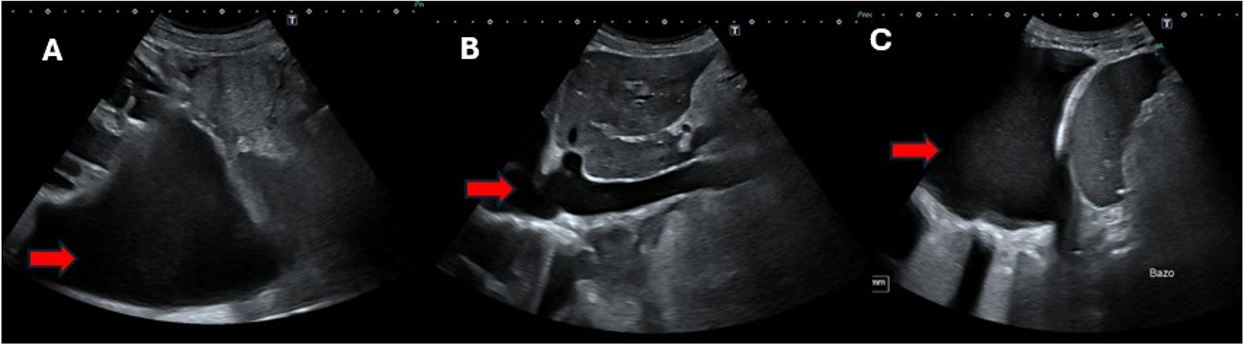

Presentamos el caso de un varón de 65 años con insuficiencia cardíaca avanzada, fracción de eyección del 19%, insuficiencia tricuspidea grave e hipertensión pulmonar, que consultó por disnea y aumento del perímetro abdominal. La ecografía descartó hipertensión portal y cirrosis. El análisis del líquido ascítico (proteínas totales 3,5 g/dL, gradiente de albúmina sérica-ascitis 2,2 g/dL y predominio de polimorfonucleares, 89%) fue compatible con peritonitis bacteriana espontánea. El paciente evolucionó favorablemente tras tratamiento antibiótico.